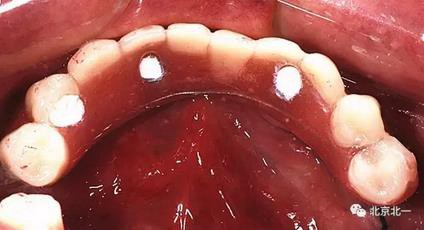

圖七:采用A04技術(shù),拔除下頜余留牙,修整骨平面。在頦孔前方傾斜植入兩枚植體,避開頦孔。減少懸臂。前牙區(qū)植入兩枚直的植體。完成即刻修復(fù)。一日得牙,缺牙后多少年來都沒有吃過蘋果的滋味,到種植牙時(shí)代,想吃什么就吃什么, 我的健康我做主。

吃出健康,吃出風(fēng)采。 吃蘋果,平平安安。健健康康。八十歲種植不是夢(mèng)想。完美人生。